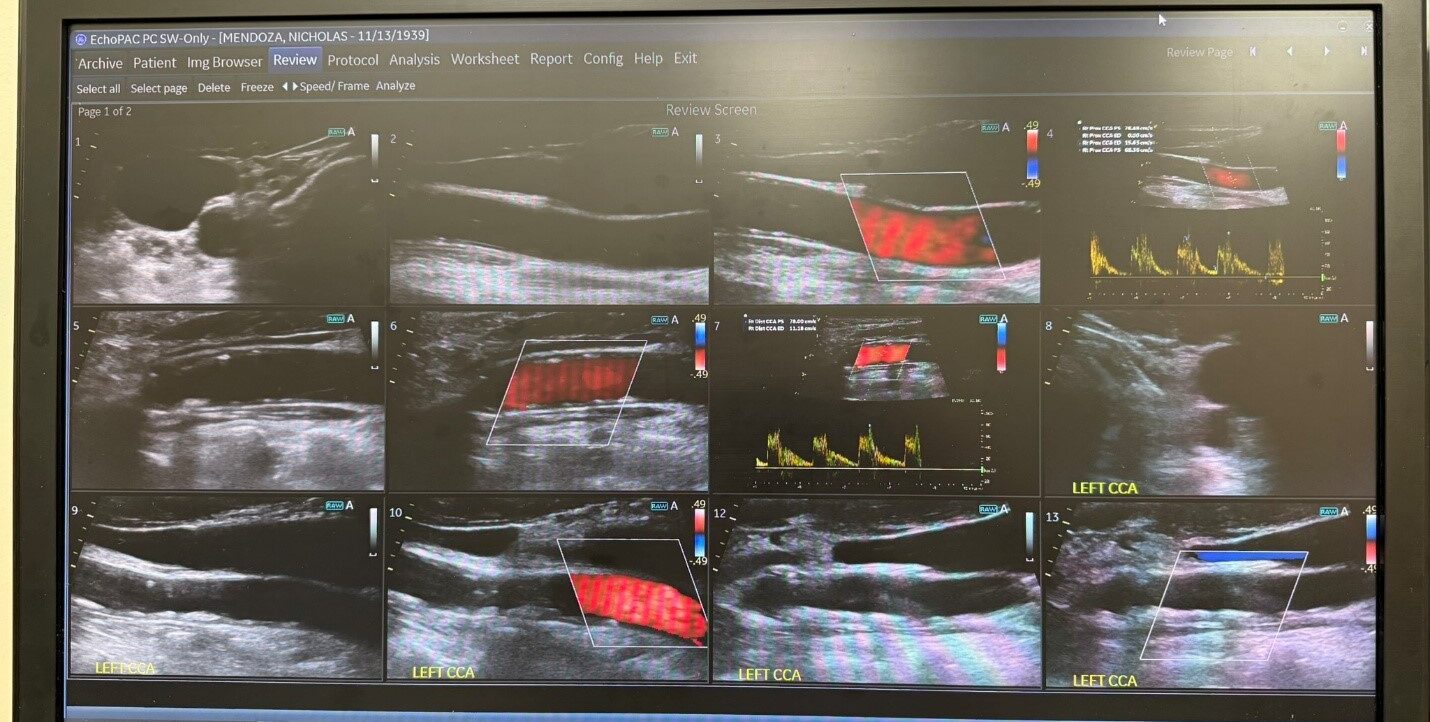

Ultrasound image showing blood flow within the carotid arteries.

Our trained staff performs carotid ultrasound to evaluate blood flow to the brain.

The test usually takes about 20 minutes. A small ultrasound probe is gently moved over the neck with gel to capture images of blood flow. There is no radiation, no needles, and the procedure is painless.